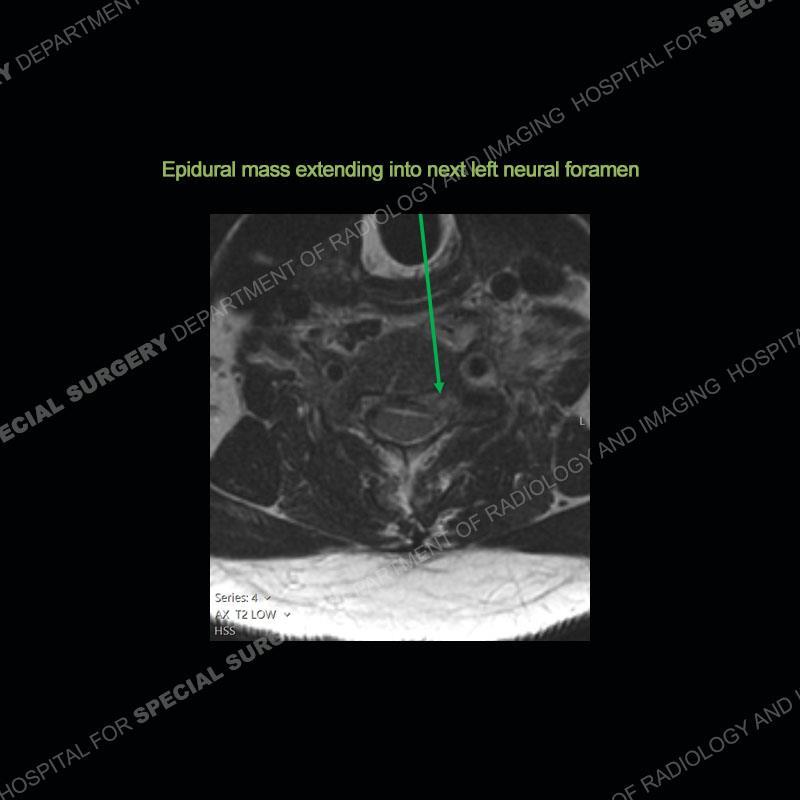

The radiographs demonstrate a prevertebral soft tissue fullness centered at C5-C6 that persists even on extension. There is a slight loss of disc height at C5-C6. The CT more readily shows the prevertebral soft tissue swelling at C5C6 where there is a punctate focus of gas. On the MRI, there is a marked amount of edema and a heterogeneous collection in the prevertebral soft tissue at C5-C6. Edema is present of the C5 and C6 vertebral bodies with a loss of the normal architecture about the disc space. A heterogeneous epidural collection has formed that causes compression of the spinal cord asymmetric to the left side and also precipitates severe left sided neural foraminal stenosis.

Diagnosis: Spontaneous Retropharyngeal Abscess (RPA) with Discitis/Osteomyelitis, Epidural Abscess, and Cord Compression

Spontaneous RPA in the non-immunocompromised, adult population is an extremely rare occurrence. RPA most frequently occurs in young children and most typically after a URI. It may be associated with torticollis in Grisel syndrome. In the adult population, the pathomechanism is not well understood with some suggesting a hematogenous spread or perhaps a seeding from the adjacent aerodigestive tract. The abscess as in this case can extend to involve the vertebral column and then the neural elements. At times, this process can be treated with antibiotic therapy alone but when there are neurologic symptoms and especially progression of neurologic symptoms, surgical intervention is warranted. In this case, given the extent of the process and the patient’s clinical situation, a corpectomy with fusion was performed in addition to antibiotics.